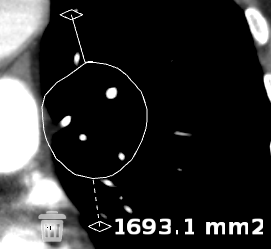

A vizsgált terület (ROI) mérésének menete:

Válassza a vizsgált terület (ROI) ![]() ikont

ikont

Kattintson a vizsgált területre

Húzza az egeret a terület meghatározásához

Engedje el az egérgombot

A középső fogóponttal  mozgathatja az ROI-t a képen, a többivel pedig nyújthatja vagy keskenyítheti.

mozgathatja az ROI-t a képen, a többivel pedig nyújthatja vagy keskenyítheti.